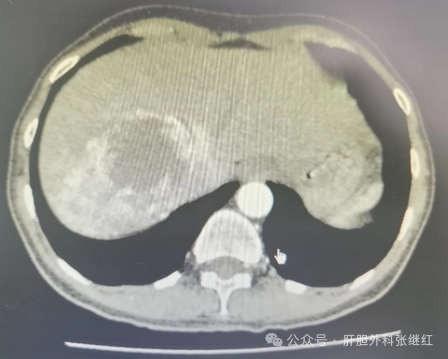

肝血管瘤是先天发育异常或后天内分泌障碍所致的肝脏良性疾病。大多数肝血管瘤体积小、生长缓慢、对机体无不良影响,不需要治疗,更不需要手术治疗。临床上肝血管瘤的手术适应证非常有限。由于肝血管瘤系良性病变,不发生癌变和转移,即使需要手术只需达到去除瘤体的目的即可,一般不需要规则性肝叶、肝段或半肝切除,这样可最大限度地保留正常肝组织。因此,目前主流观点认为,治疗肝血管瘤的最佳手术方法是肝血管瘤切除或剥除术。在微创技术引领外科手术发展方向的今天,具有微创优势的腹腔镜肝血管瘤切除术逐渐得到广大医生和患者青睐。

腹腔镜肝血管瘤切除的手术适应证与开腹手术相同,主要局限于有压伴有症状、严重并发症、生长迅速、伴有kasabach -Merritt综合征(血小板异常消耗导致出血倾向)、不除外恶变等危险因素及特殊情况有破裂风险或损害正常结构和功能风险的瘤体巨大的肝血管瘤。具体手术适应证参见本公众号文章肝血管瘤患者如何决策抉择?